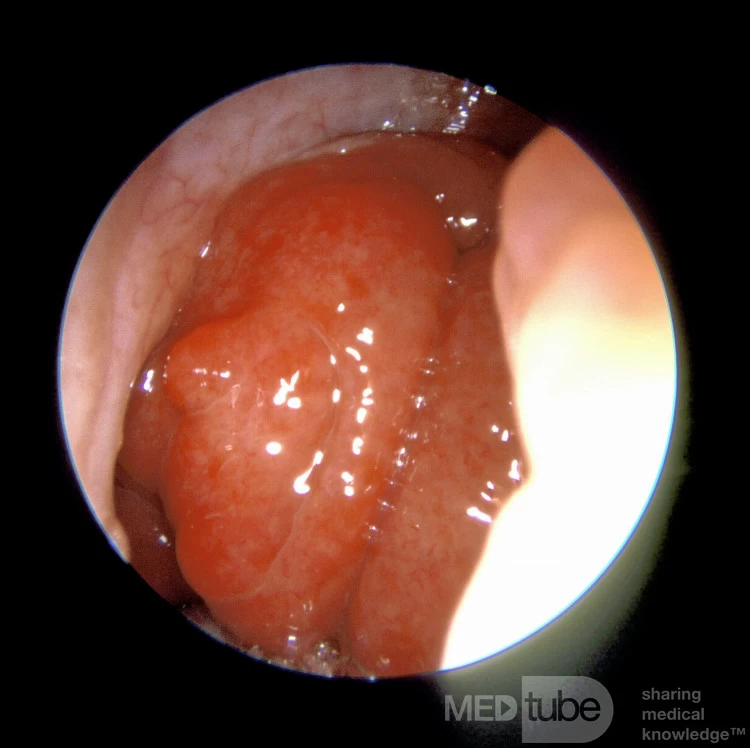

Bức ảnh nội soi này cho thấy amidan to chặn lỗ mũi của người lớn này. Amidan to ở người lớn tương đối hiếm gặp và người ta phải nghĩ đến các chẩn đoán có thể khác.